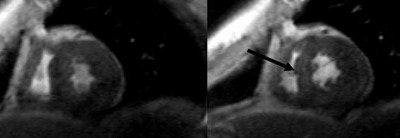

![]() |

| Two midventricular images at 10 and 40 μg/kg/min. of dobutamine. The arrow (at 40 μg) indicates absence of septal wall thickening, which is indicative of inducible myocardial ischemia. Image courtesy of Dr. Caroline Janssen. |